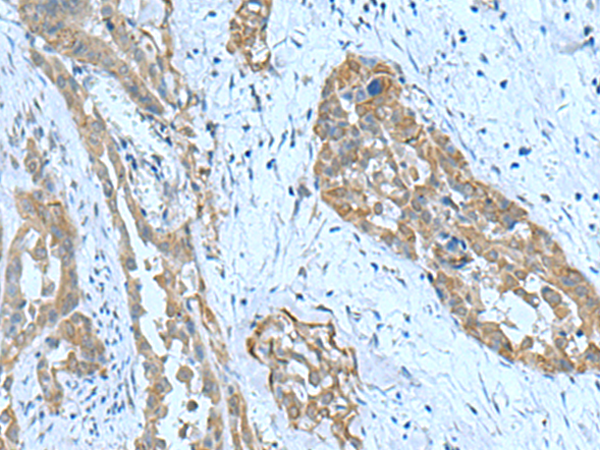

IHC positive control: |

Human thyroid cancer |

IHC Recommend dilution: |

100-300 |